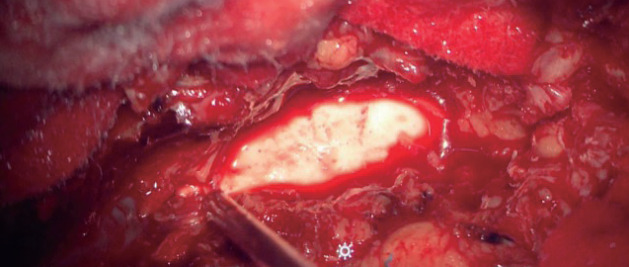

骨水泥增强椎弓根螺钉内固定是一种被广泛接受的治疗骨质疏松性骨折的方法,但它具有固有的风险,特别是与骨水泥泄漏和栓塞有关。本研究旨在分析一例水泥内固定术后并发症的临床病例,并对相关文献进行详细的复习。一名70岁的患者接受了L2-L4椎弓根螺钉内固定和聚甲基丙烯酸甲酯增强,导致水泥渗漏到椎管中并随后发生肺栓塞。经翻修手术和栓塞保守治疗后,患者病情稳定,表明保守治疗水泥栓塞是有效的。为了补充本病例,我们进行了全面的文献回顾,以探讨与骨水泥增强术相关的并发症的原因、预防和治疗。研究结果表明,尽管骨水泥增强椎弓根螺钉内固定仍然是治疗骨质疏松性骨折的主要技术,但通过适当的治疗方案,相关风险是可控的。本研究通过强调与骨水泥固定相关的风险和解决方案,从而有助于改善患者的预后和制定标准化的治疗指南,对医疗保健专业人员具有实际意义。

Cement-augmented pedicle screw instrumentation is a widely accepted method for managing osteoporotic fractures, but it carries inherent risks, particularly related to cement leakage and embolism. This study aimed to analyze a clinical case of complications following cement fixation and provide a detailed review of relevant literature. A 70-year-old patient underwent transpedicular screw instrumentation from L2-L4 with polymethyl methacrylate augmentation, which resulted in cement leakage into the spinal canal and subsequent pulmonary embolism. After revision surgery and conservative treatment for the embolism, the patient's condition stabilized, demonstrating that conservative measures can be effective in managing cement embolism. To complement this case, a comprehensive literature review was conducted to explore the causes, prevention, and treatment of complications related to cement augmentation. The findings support that while cement-augmented pedicle screw instrumentation remains a leading technique for osteoporotic fractures, the associated risks are manageable with proper treatment protocols. This study holds practical significance for healthcare professionals by highlighting both the risks and solutions associated with cement fixation, thus contributing to improved patient outcomes and the development of standardized treatment guidelines.